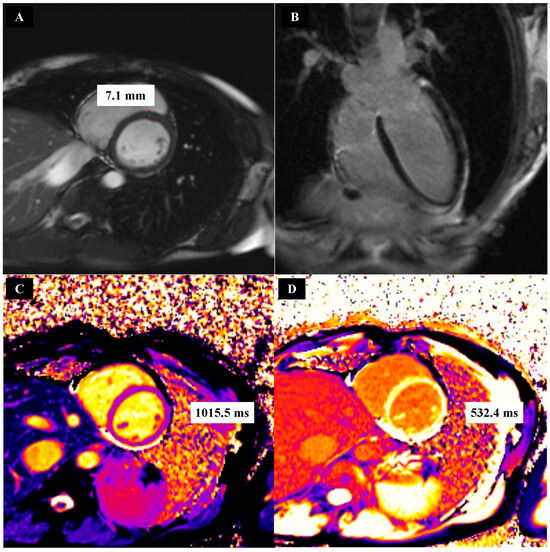

| whole myocardium [ms] a | 1038.15 ± 2.98 | 1031.56 ± 3.65 | - |

| whole myocardium [%] a | 30.23 ± 0.84 | 25.08 ± 0.36 | 0.01 |